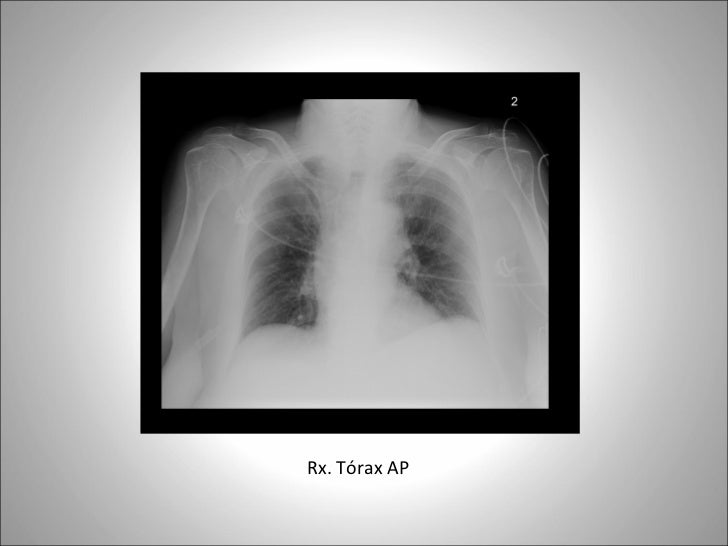

12. 16. <ul><li>Rx. Tórax AP </li></ul>